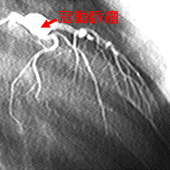

冠動脈といわれてもピンとこないかもしれませんが、「心筋梗塞」「狭心症」という病名には、なじみがあるでしょう。冠動脈とは、心臓全体に張り巡らされて、心臓自体に栄養を供給している血管で、これがつまると「心筋梗塞」となり、心臓が止まってしまいます。狭くなると「狭心症」といって、心臓の動きが悪くなるために胸が痛くなったり、倒れたりします。

冠動脈は、大動脈から右と左に二本でます。右は主に右心室に、左は左心室に分布します。心臓で一番大事なポンプは左心室ですから、左心室に栄養を送っている左冠動脈がつまると、命取りになります。